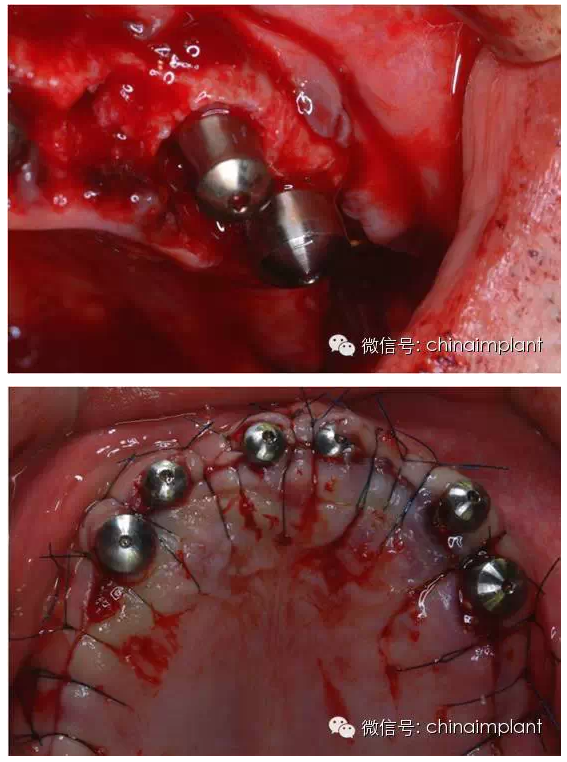

之前的時(shí)候,使用圓錐形基臺(tái),但是附著的力量容易分散。(最近由于費(fèi)用的問(wèn)題多使用UCLA形態(tài)的基臺(tái))

此案例為術(shù)后兩周戴臨時(shí)牙。過(guò)去因?yàn)閾?dān)心感染的問(wèn)題,一個(gè)月以內(nèi)帶臨時(shí)牙也叫做即刻負(fù)重或者早期負(fù)重。(現(xiàn)在當(dāng)天戴臨時(shí)牙(即刻復(fù)重)的情況也非常常見).